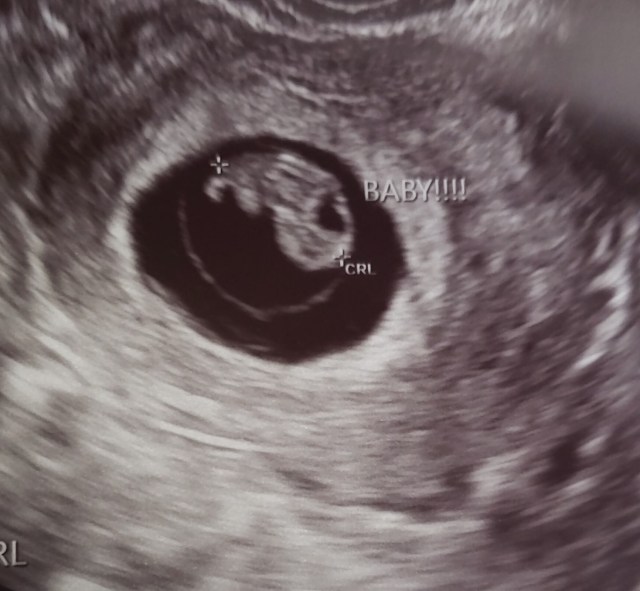

I saw the familiar black circle and an funky animal cracker shaped blob in the top right corner of the circle. My mind went blank and my body went numb. Why wasn’t she saying anything. I turned to look away as she said “There’s the heartbeat, Mom. Congratulations.” I said flatly that I couldn’t see it. She was definitely lying. She moved it around a little more and zoomed in and by golly there it was! A flickering white line. I melted. I literally melted, you guys. Everything unclenched and I felt a lightness I haven’t felt in weeks.

She went over everything from before. Dandelion measuring 8 weeks. I’ll be 8 weeks tomorrow. 16mm long. Good looking yolk sack. Due date 23 October. Heart rate at 181. Then she said they needed to do another blood test to check my blood type. So we followed her out and she asked one of the nurses to do it. Then she looked at both of us, congratulated us again and left. That was it. I did my last ever (hopefully) blood draw at my beloved clinic and then we just left. There really should be more fan fair when one graduates from an ivf clinic.